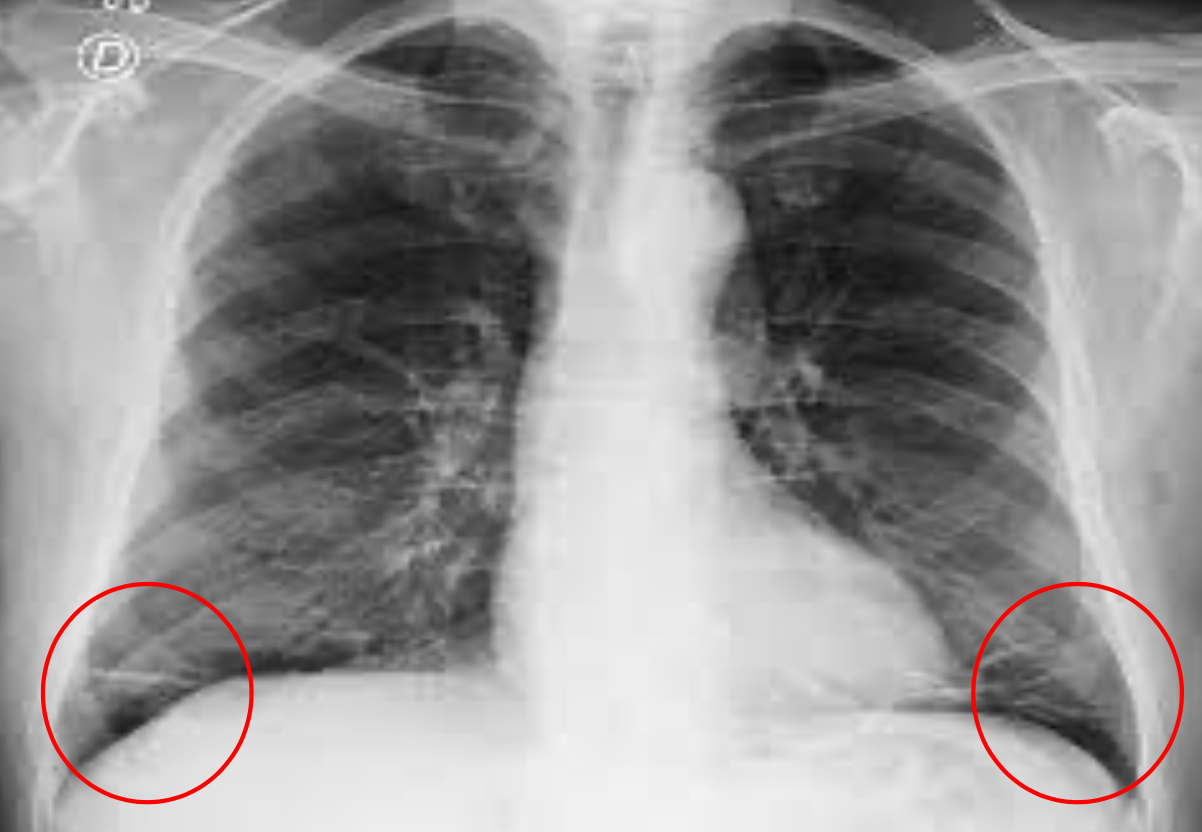

Rx en insuficiencia cardiaca

A: edema alveolar B: líneas B de Kerley C: cardiomegalia D: dilatación de vasos en lóbulos superiores E: derrame pleural

130

Insuficiencia cardiaca